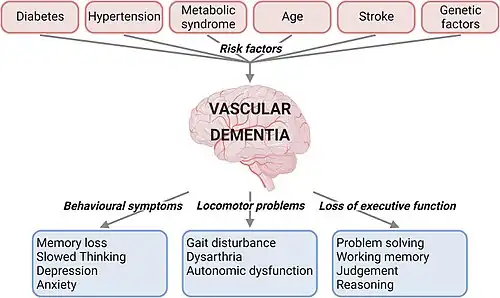

The disease is described as both a mental and behavioral disorder within the ICD-11.[8] Signs and symptoms are cognitive, motor, behavioral, and for a significant proportion of people, also affective. These changes typically occur over a period of 5–10 years. Signs are typically the same as in other dementias, but mainly include cognitive decline and memory impairment of sufficient severity as to interfere with activities of daily living, sometimes with presence of focal neurological signs, and evidence of features consistent with cerebrovascular disease on brain imaging (CT or MRI).[4][5]

The neurological signs localizing to certain areas of the brain that can be observed are hemiparesis, bradykinesia, hyperreflexia, extensor plantar reflexes, ataxia, pseudobulbar palsy, as well as gait problems and swallowing difficulties. People have patchy deficits in terms of cognitive testing. They tend to have better free recall and fewer recall intrusions when compared with people having Alzheimer's disease.[9] In the more severely affected people, or those affected by infarcts in Wernicke's or Broca's areas, specific problems with speaking called dysarthria and aphasias may be present.[2][5]

In small vessel disease, the frontal lobes are often affected. Consequently, people with vascular dementia tend to perform worse than their Alzheimer's disease counterparts in frontal lobe tasks, such as verbal fluency, and may present with frontal lobe problems: apathy, abulia (lack of will or initiative), problems with attention, orientation, and urinary incontinence. They tend to exhibit more perseverative behavior. People with vascular dementia may also present with general slowing of processing ability, difficulty shifting sets, and impairment in abstract thinking. Apathy early in the disease is more suggestive of vascular dementia.[2][5]

Risk factors for vascular dementia include increasing age, hypertension, smoking, hypercholesterolemia, diabetes mellitus, cardiovascular disease, and cerebrovascular disease.[2][5] Other risk factors include lifestyle, geographic origin, and APOE-ε4 genotype.[2][5]